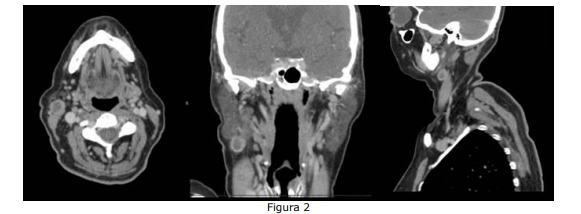

Paciente com diagnóstico de CEC de língua metastático para linfonodo cervical realizou TC de face e pescoço, mostrada na Figura 2 abaixo:

Enunciado 4483720-1

Com base na Figura 2, assinale a alternativa que indica o nível cervical em que se encontra a metástase em questão.